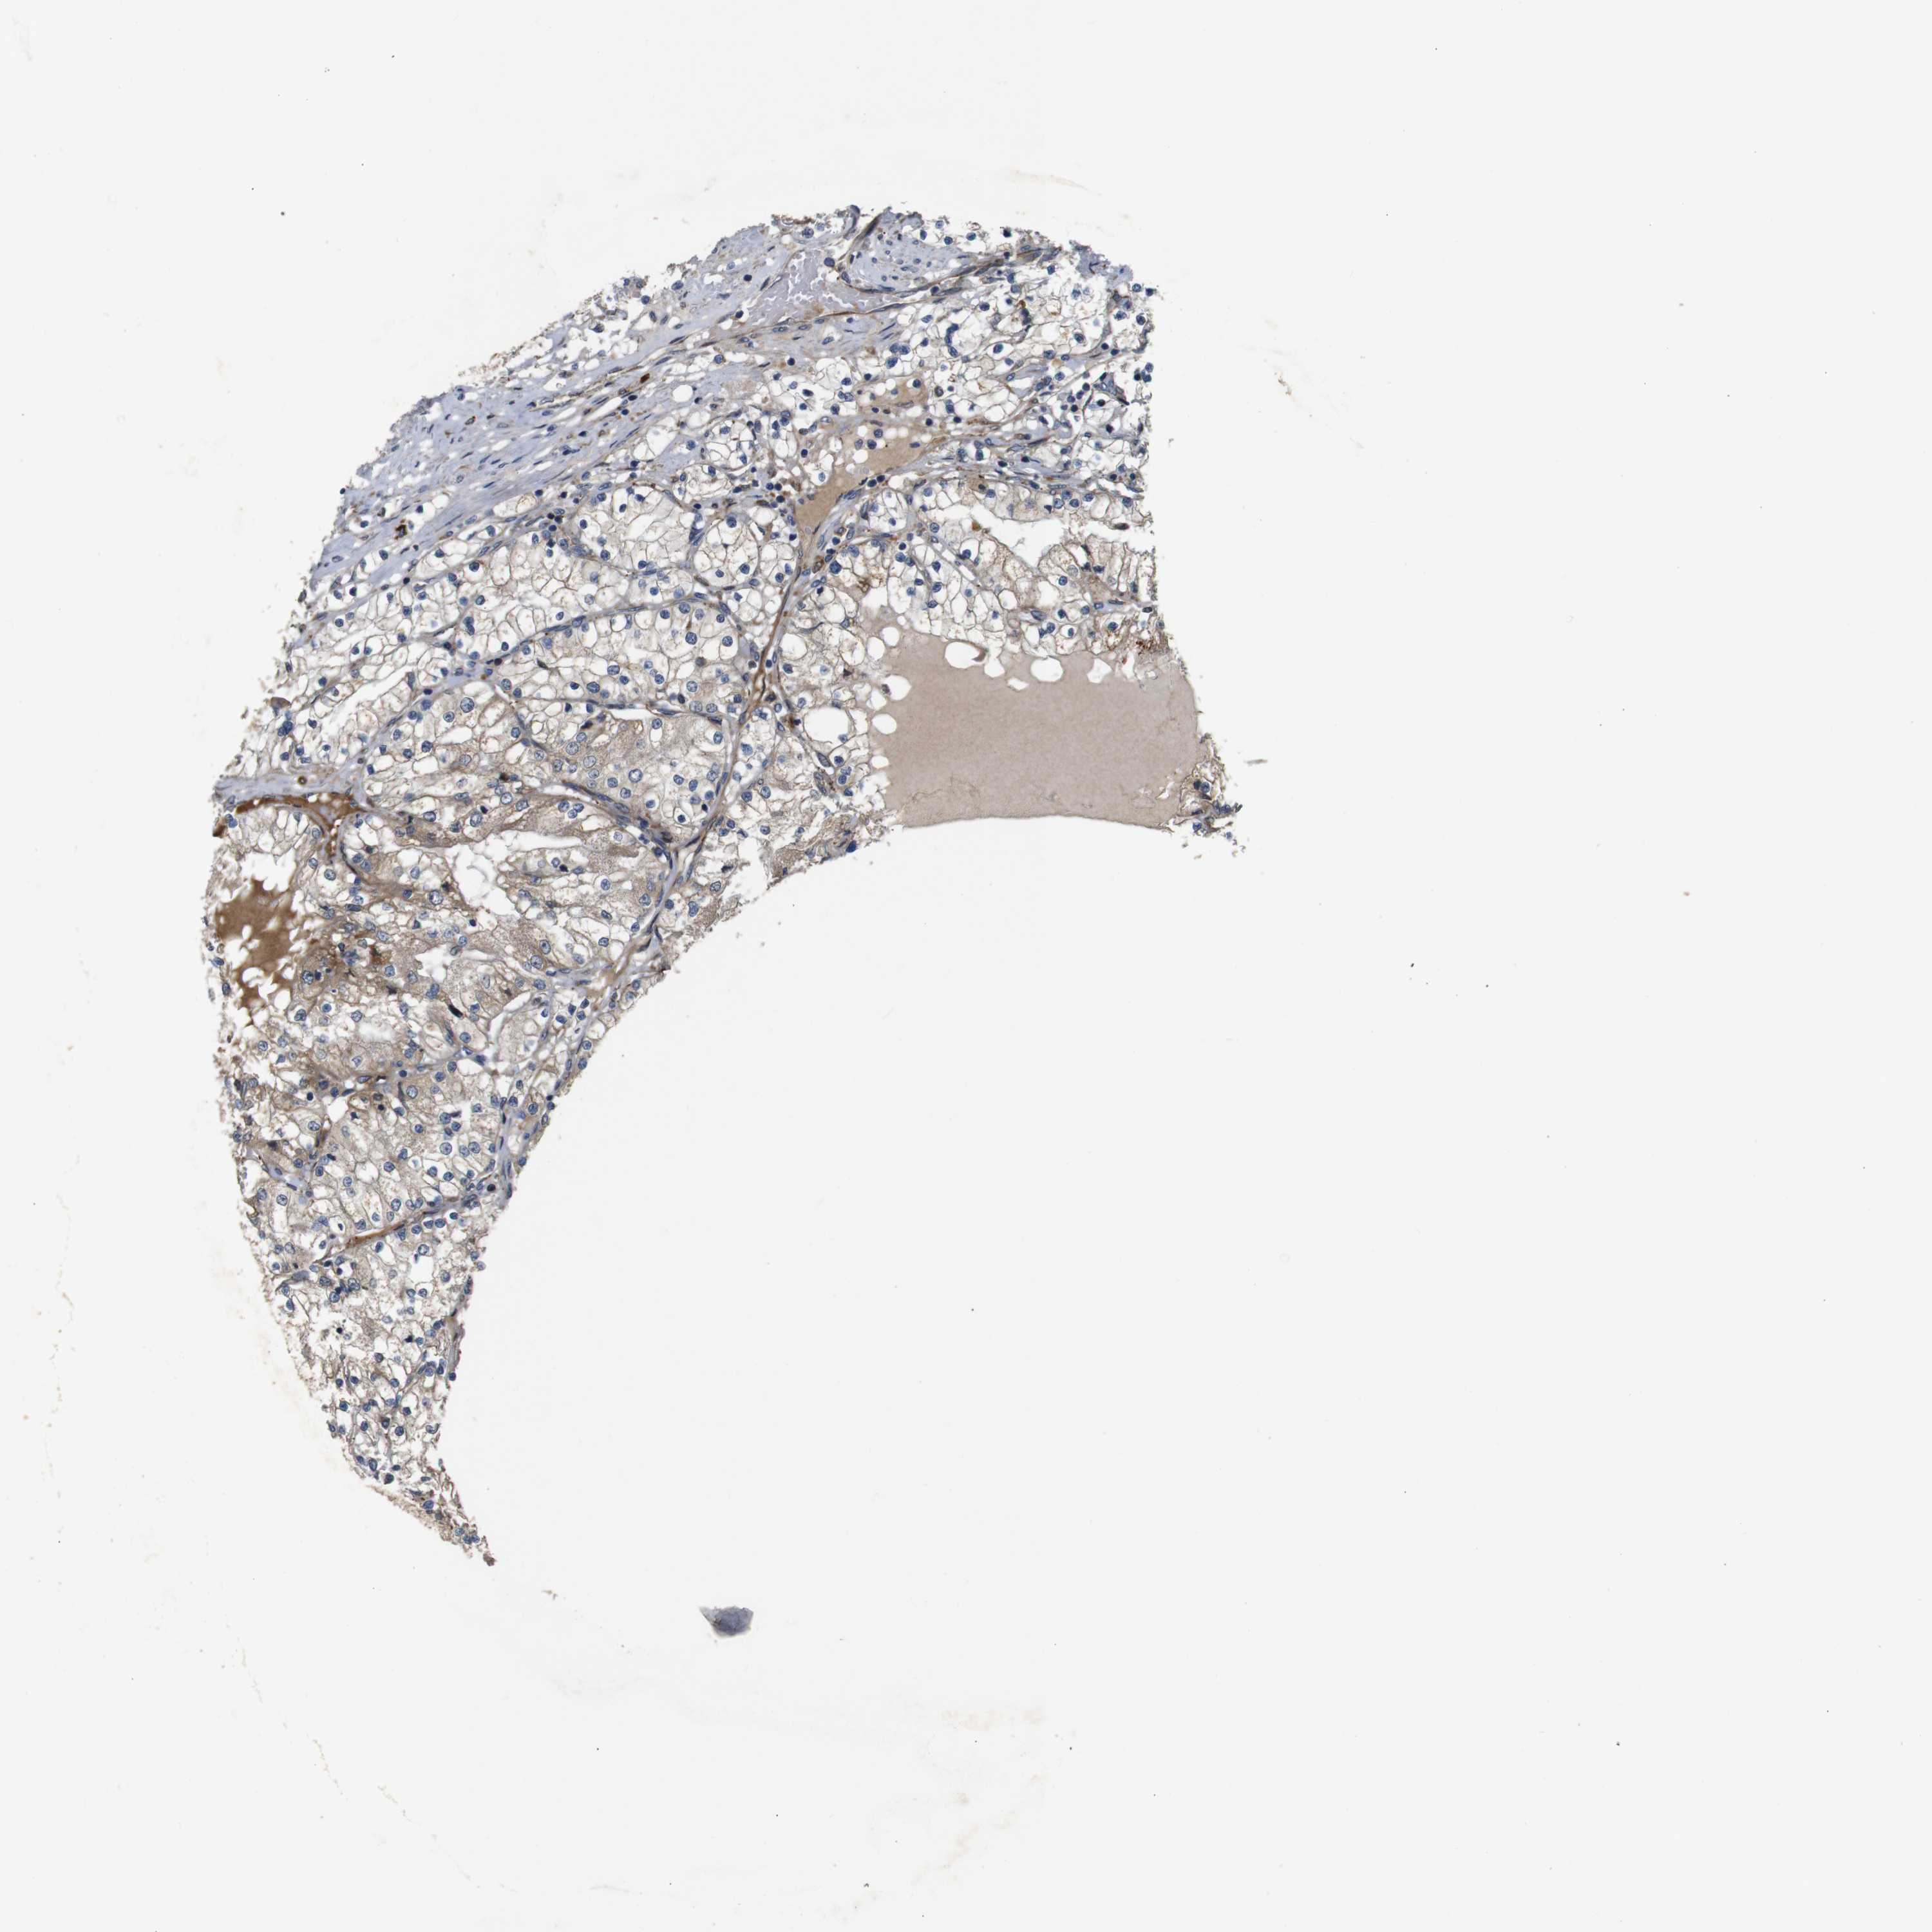

KIDNEY RENAL CLEAR CELL CARCINOMA (VALIDATION) - Interactive survival scatter ploti

The Survival Scatter plot shows the clinical status (i.e. dead or alive) for all individuals in the patient cohort, based on the same data that underlies the corresponding Kaplan-Meier plots. Patients that are alive at last time for follow-up are shown in blue and patients who have died during the study are shown in red.

The x-axis shows the expression levels (FPKM) of the investigated gene in the tumor tissue at the time of diagnosis. The y-axis shows the follow-up time after diagnosis (years). Both axes are complimented with kernel density curves demonstrating the data density over the axes. The top density plot shows the expression levels (FPKM) distribution among dead (red) and alive patients (blue). The right density plot shows the data density of the survived years of dead patients with high and low expression levels respectively, stratified using the cutoff indicated by the vertical dashed line through the Survival Scatter plot. This cutoff is automatically defined based on the FPKM cutoff that minimizes the p-score. The cutoff can be changed by dragging the vertical line or by entering a cutoff value in the square labeled "Current cut-off".

Under the Survival Scatter plot the p-score landscape (black curve; left axis) is shown together with dead median separation (red curve; right axis). Dead median separation is the difference in median mRNA expression between patients who have died with high and low expression, respectively. It is calculated as follows: median FPKM expression of dead patients with high expression - median FPKM expression of dead patients with low expression. This is intended to aid the user in visually exploring custom cutoffs and the associated p-scores and dead median separation.

Individual patient data is displayed and can be filtered by clicking on one or more of the category buttons on the top of the page. Categories describing expression level and patient information include: high, low, alive, dead, female, male and tumor stages. The scale of the x-axis can be toggled between linear and log-scale by clicking on the "x log" button. Mouse-over function shows TCGA ID, patient information and mRNA expression (FPKM) for each patient.

& Survival analysisi

Kaplan-Meier plots summarize results from analysis of correlation between mRNA expression level and patient survival. Patients were divided based on level of expression into one of the two groups "low" (under cut off) or "high" (over cut off). X-axis shows time for survival (years) and y-axis shows the probability of survival, where 1.0 corresponds to 100 percent.

UBE2G2 is not prognostic in Kidney Renal Clear Cell Carcinoma (validation)

Best expression cut offi

Based on the FPKM value of each gene, patients were classified into two groups and association between prognosis (survival) and gene expression (FPKM) was examined. The best expression cut-off refers the FPKM value that yields maximal difference with regard to survival between the two groups at the lowest log-rank P-value. Best expression cut-off was selected based on survival analysis .

When clicking on this number, the vertical dashed line indicating cut-off, the interactive survival plot, and the Kaplan-Meier curve will be adjusted to show results based on the best expression cut-off.

: 25.02

P scorei

Log-rank P value for Kaplan-Meier plot showing results from analysis of correlation between mRNA expression level and patient survival.

N/A

5-year survival highi

5-year survival for patients with higher expression than the expression cutoff.

For melanoma and glioma, 3-year survival is shown.

5-year survival lowi

5-year survival for patients with lower expression than the expression cutoff.

Average pTPM 26.7

Number of samples 100